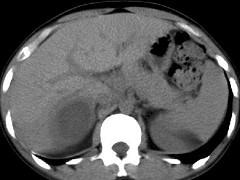

问题 女,25岁,上腹疼痛不适,低热,有阿米巴痢疾病史,CT检查发现肝右叶低密度病变,如图,最可能的诊断是 ( )

选项 A.原发性肝癌 B.肝血管瘤 C.肝错构瘤 D.阿米巴肝脓肿 E.肝转移瘤

答案 D